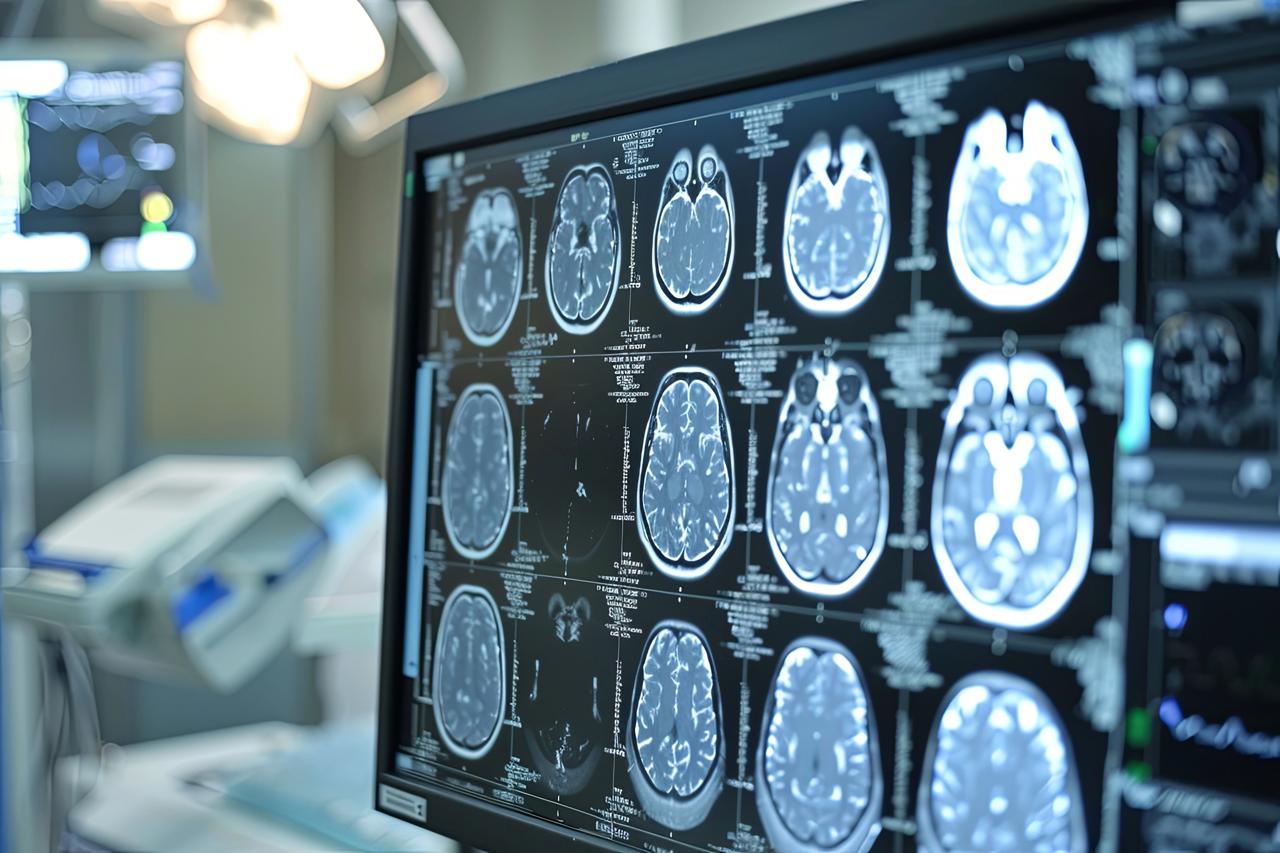

Roma, 27 ott. (Adnkronos Salute) – Una volta erano considerate delle neoplasie rare, ma oggi i gliomi sono sempre più diffusi. In Italia i casi annui ammontano a oltre 3mila e corrispondono al 40% di tutti i tumori cerebrali primitivi. Tra i gliomi, quelli di basso grado di frequenza più rara rappresentano una sfida clinica rilevante anche per la loro evoluzione e l’assenza di trattamenti mirati, oltre alla resistenza che dimostrano ai trattamenti convenzionali. Sono malattie orfane di cui si parla poco anche fra i clinici, tra le istituzioni e sui media. Perciò la Fondazione Aiom (Associazione italiana di oncologia medica) ha lanciato nei mesi scorsi ‘I gliomi’, una campagna nazionale online di formazione e informazione. Sono stati organizzati webinar rivolti agli oncologi medici e alle altre figure sanitarie coinvolte nel team multidisciplinare. Sono stati indirizzati a pazienti e caregiver ulteriori eventi online insieme a un’attività di sensibilizzazione sui principali social media. I risultati dell’iniziativa sono presentati oggi in una conferenza stampa virtuale promossa da Fondazione Aiom. Il progetto è stato realizzato con il contributo non condizionante del Gruppo Servier in Italia. “Sono tumori cerebrali molto complessi e che spesso vengono diagnosticati in età giovanile – afferma Saverio Cinieri, presidente di Fondazione Aiom – Si sviluppano da cellule del cervello chiamate gliali e possono avere una prognosi variabile, ma potenzialmente a lungo termine. La gestione della patologia richiede una stretta collaborazione fra neurochirurgo, radioterapista e oncologo medico. Attraverso il bisturi è possibile rescindere la massa tumorale oppure eseguire una biopsia grazie a nuove e sofisticate tecnologie. La radioterapia permette di ridurre il rischio di recidiva o eliminare quella parte di cancro che non è stato possibile rimuovere chirurgicamente. Viene somministrata insieme alla chemioterapia e le sedute sono di solito diluite nel corso del tempo, per limitare l’impatto degli effetti collaterali. Infine, l’oncologo medico deve scegliere i farmaci da somministrare e deve selezionarli valutando le condizioni cliniche del singolo paziente”. “Anche per il trattamento dei gliomi, in particolare quelli di basso grado, si può ricorrere all’oncologia di precisione che potrà ridisegnare la pratica clinica nel prossimo futuro – illustra Enrico Franceschi, direttore dell’Oncologia del sistema nervoso all’Irccs Istituto delle scienze neurologiche di Bologna – E’ molto importante verificare la presenza o meno delle mutazioni Idh1 e Idh2. Questi biomarcatori indicano specifiche patologie caratterizzate da una prognosi decisamente più favorevole e maggiore sensibilità dei gliomi alla radio e chemioterapia. Al momento della diagnosi è quindi essenziale l’esecuzione precoce di alcuni test molecolari per identificare al meglio i diversi sottotipi di gliomi. Tra le terapie di nuova generazione vi è anche vorasidenib, un farmaco orale inibitore Idh1 e Idh2 che ha dimostrato di essere un trattamento efficace nel posticipare la radio e chemioterapia nei gliomi di basso grado ed è una rilevante innovazione medico-scientifica”. “Come tutti i tumori cerebrali – prosegue Cinieri – anche i gliomi di basso grado hanno un forte impatto sulla vita del paziente. Sono tante le complicanze che possono verificarsi durante l’intero percorso di cura, perché intervenire sul cervello umano con radiazioni ionizzanti o con interventi chirurgici può comprometterne alcune funzioni basilari. Tra queste vi sono le capacità di parlare o di movimento. Si rendono a volte necessari interventi riabilitativi di logopedisti, fisioterapisti o altri professionisti come lo psiconcologo. Ricevere la notizia della presenza di un tumore in una zona così particolare e delicata porta quasi sempre a depressione e ansia, soprattutto quando il primo approccio è un periodo di osservazione privo di un trattamento attivo. Le terapie innovative sono in grado di prolungare in modo significativo la sopravvivenza libera da progressione e garantiscono un buon profilo di sicurezza e tollerabilità”.”Ancora una volta l’oncologia medica è centrale nella gestione multidisciplinare di neoplasie estremamente complesse ed insidiose – sottolinea Franceschi – Il trattamento dei gliomi inizia nel momento della diagnosi che deve essere sia morfologica che molecolare. Esistono infatti 150 diversi sottotipi di neoplasia cerebrale ed è fondamentale riconoscere fin da subito le caratteristiche del singolo caso per poter così selezionare le terapie più appropriate. Fino a pochi anni fa avevamo a disposizione solo chirurgia, radioterapia e chemioterapia. Ora i farmaci ad azione mirata sono una realtà anche nella cura dei tumori cerebrali che esprimano specifiche alterazioni molecolari”. “Nasce da questo rapido progresso nei trattamenti la nostra campagna d’informazione rivolta principalmente a specialisti clinici e pazienti – conclude Cinieri – L’oncologia medica è in costante evoluzione ed è compito di associazioni e fondazioni garantire sempre un aggiornamento scientifico qualificato. L’oncologia di precisione è una realtà consolidata in molte forme di cancro ed è un approccio che indirizza sempre più le nostre scelte terapeutiche. Sta portando a risultati davvero interessanti ed inimmaginabili fino a pochi anni fa anche per neoplasie rare e difficili da trattare come i gliomi di basso grado Idh mutati”.